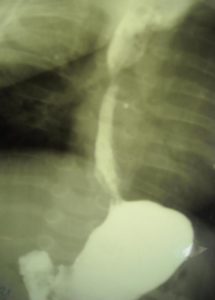

Рентген с использованием контрастного вещества сульфата бария, которое вводится через рот. Этот метод позволяет оценить функциональные свойства пищевода и других органов ЖКТ, включая перистальтику.

Фиброгастроскопия — эндоскопическое исследование состояния слизистой оболочки ЖКТ с помощью зонда с камерой. Визуальный осмотр позволяет оценить эндоскопические признаки.